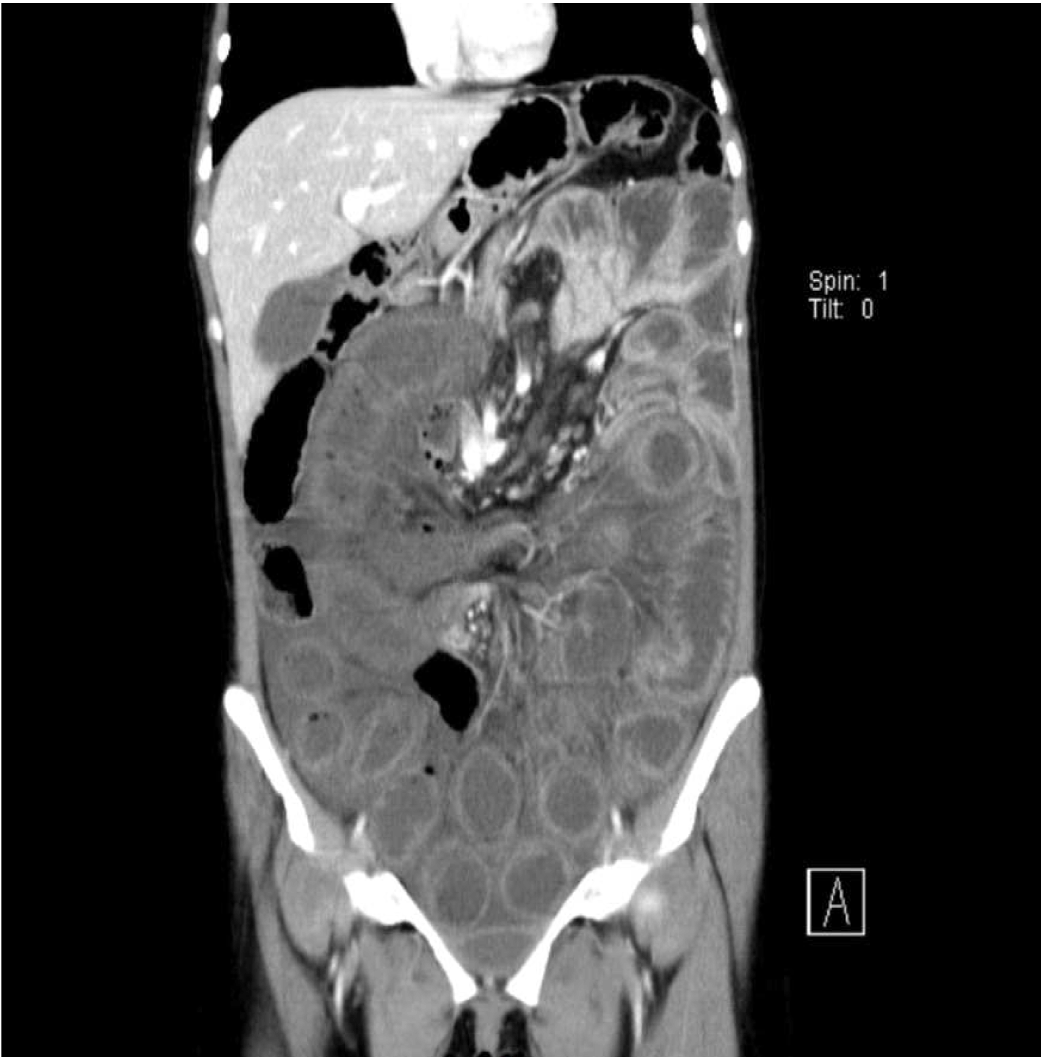

A 37-year-old female presented to the emergency department with diffuse abdominal pain, developing suddenly an hour ago. The pain was severe, not colicky and radiated through to her back. Sitting upright and leaning forward relieved the pain. She was also complaining from nausea and vomiting. She was passing flatus. Before, she had not experienced any similar pain. Her vital signs were normal. In her physical examination, there was diffuse tenderness, and rebound, guarding in right upper and lower quadrants. In blood gas analysis, her venous blood pH: 7.19, HCO3: 16 mmol/L, CO2: 47 mmHg, lactate 4.2 mmol/L, base excess: 10.6 mmol/L. In her total blood count, white blood cell was 13400/L. Her liver function tests were minimally elevated. As her pain was persistent and unexplained. A computed tomography scan of the abdomen and pelvis with intravenous contrast demonstrated dilatation and left migration of the loops of jejenum, migration of inferior mesenteric vein to the left, and free fluid in abdomen (Figure 1) and (Figure 2). With the prediagnosis of internal herniation, fluid resuscitation and supportive care were initiated for preparation for surgery. In the first, operation laparotomy with mid line incision made, 500 cc fluid was aspirated, it was seen that 50 cm segment of the terminal ileum was herniated medial to cecum (paracecal hernia), ileum was extracted from the defect. It was seen that loops of jejenum and terminal ileum up to 50 cm proximal to ileocecal valve were dilated and viable. Hot compresses were situated. Resection was not applied due to revascularization of ischemic loops was seen after 10 minutes. The defect was repaired and operation was terminated. After three days, patient deteriorated; in the exploration ischemia was detected beginning from 10 cm proximal of terminal ileum up to the 200 cm ileum. Ischemic loops were dissected, serosal tearing in ileum and sigmoid colon repaired. Efferent and afferent tips together subtracted from right upper quadrant. After four days, probably from micro perforations and ventilator associated pneumonia, in blood culture first methicillin resistant Staphylococcus auerus then Pseudomonas aeruginosa proliferated, despite of full septic shock treatment (fluid therapy; vancomycin, clindamycin, gentamycin antibiotic therapy; vasopressors with noradrenalin and dopamine), the patient died in intensive care unit due to sepsis and multi-organ failure. | ||||||

In autopsies, internal hernia has been reported to range from 0.2–0.9% [2]. In the reality, we know that 5.8% cases of small bowel obstruction are due to internal hernia [4]. Internal herniation should be considered as a differential diagnosis in patients presenting with symptoms of small bowel obstruction without a history of prior abdominal surgery. Normally, standard hernias results from defects in the retaining walls of the abdomen. But internal hernias are due to the organ protrusion through an opening or pouch of the peritoneum. Patient may be asymptomatic or may have ileus symptoms and findings like constant epigastric pain or intermittent colicky periumbilical pain. There may be nausea or vomiting. The severity of the pain is related to the presence of ischemia or necrosis. As no specific symptoms are associated with the condition, it is rarely diagnosed preoperatively. Clinical examination is non-specific and laboratory findings are rarely helpful. Although the occurrence is rare, delayed diagnosis and treatment are associated with a high mortality rate. Abdominal CT scan is important for intestinal obstruction [6]. Computed tomography scan gives information about location of obstruction, the possible underlying causes, such as malignancy, stenosis within the bowel wall, and other intraluminal problems such as intussusception, feces or or Bezoar like substances [7]. Computed tomography scan has become the first-line imaging technique in patients with suspected acute abdomen. Etiologies of acute abdomen like internal hernias are often difficult to identify with physical examination [8]. Computed tomography scan showed classic signs of internal herniation as 'Whirlpool sign', crowding of bowel loops in the upper compartment and the absence of cecum in the right iliac fossa, replacement of abdominal organs and vasculature. If strangulation of the intestine is suspected including other causes also, an internal hernia should be considered as in our case. Delay in diagnosis and treatment is often observed in internal hernia cases and results high mortality rate of up to 49% [9]. In the operation, often intestinal obstruction associated with non-viable bowel detected. So the treatment invariably requires urgent surgery. Usually, open surgery is performed. Only a few cases of laparoscopic hernia management have been reported [10] . If there is intestinal necrosis, an adequate resection is mandatory. Nevertheless, there is no clear and established consensus on surgical management when the herniated contents are grossly viable. | ||||||